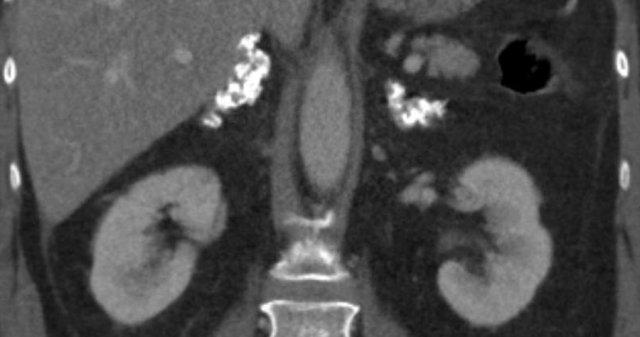

Hình ảnh cắt ngang và cắt vành cho thấy u tủy mỡ lớn bên phải kèm chảy máu.

Hình ảnh bên phải là phim chụp theo dõi.